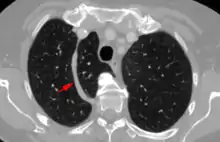

In human anatomy, an azygos lobe is a normal anatomical variation of the upper lobe of the right lung.[1] It is seen in 1% of the population. Embryologically, it arises from an anomalous lateral course of the azygos vein,[2] in a pleural septum within the apical segment of the right upper lobe or in other words an azygos lobe is formed when the right posterior cardinal vein, one of the precursors of the azygos vein, fails to migrate over the apex of the lung and penetrates it instead, carrying along two pleural layers that invaginates into the upper portion of the right upper lobe. As it has no bronchi, veins and arteries of its own or corresponding alteration in the segmental architecture of the lung, so it is not a true (misnomer), or even accessory, pulmonary lobe, but rather an anatomically separated part of the upper lobe.

An azygos lobe is usually an incidental finding on chest x-ray or CT scan, and is not associated with any morbidity.[3][4] However, it can cause technical problems in thoracoscopic procedures.[5]